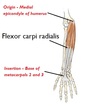

What are the origin and insertion sites of muscle A?

Origin - Medial epicondyle of humerus

Insertion - Base of metacarpals 2 and 3

A - Flexor carpi radialis